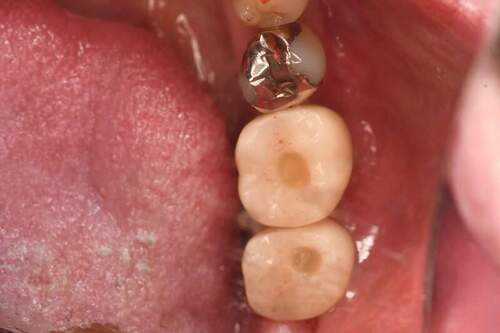

インプラント治療の症例4

口腔内写真

- Befor

- After

| 年齢 | 50代・男性 |

|---|---|

| 主訴 | 部位:左下6番7番 主訴:左下奥歯腫れて痛い。 |

| 治療内容 | 左下6番抜歯、左下6番7番骨造成、インプラント埋入 |

| 治療費 | 合計:1,232,000円 ・内訳 診断料:55,000円 サージカルガイド2本:66,000円 GBR:110,000円×2本 埋入料:165,000円×2本 静脈内鎮静麻酔:77,000円 2次OPE:22,000円×2本 仮歯:55,000円×2本 上部構造(フルジルコニア):165,000円×2本 (2023年1月現在) |

| 治療期間 | 約8ヶ月 |

| 治療方針 | 元々支台歯に負荷がかかりやすいとされている延長ブリッジを抜歯し、1本単体でしっかりかめるようにインプラントを2本埋入した。骨吸収も進んでいたため、※GBR法で骨造成を同時に行った。 治療と並行して、全顎的な歯周病治療も行い、今後は歯周病が進行しないよう、こまめにメンテナンスに通っていただく。 |

| 特記事項 | ※1 GBR・・・骨再生誘導法。骨の高さや厚みを人工骨や人工膜などを使用し再生する方法 |

| 担当者所見 | 6番は歯根分割された被せ物が7番の欠損部との延長ブリッジとされており、強い咬合と歯周病も相まって負荷がかかり動揺し、歯として機能しなくなったため、抜歯となった。 |